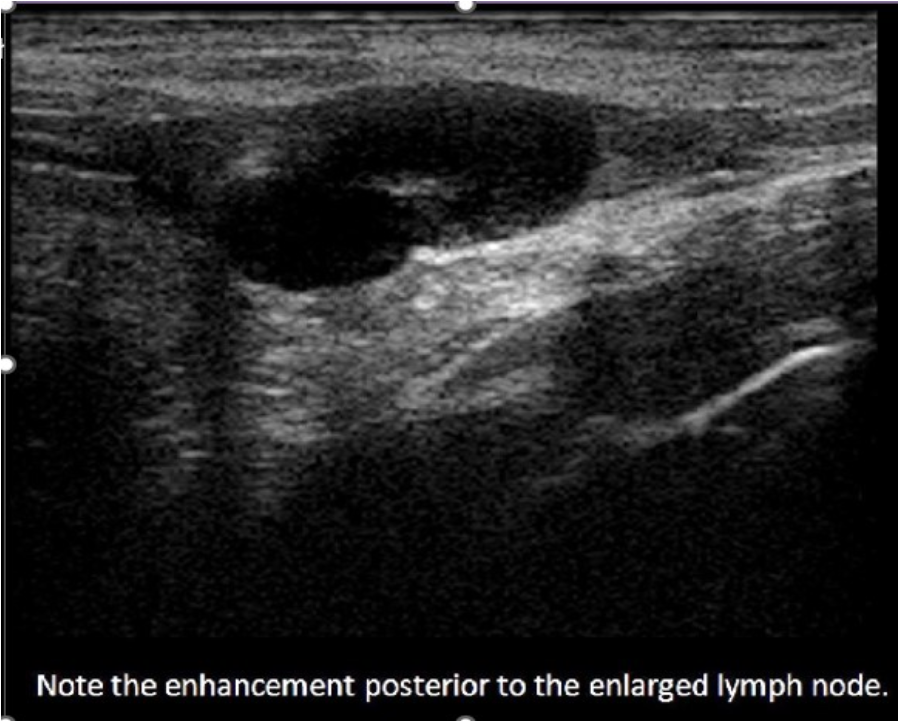

Which of the following statements is true regarding retroperitoneal lymph nodes?

C. Abnormal lymph nodes exhibit posterior enhancement.

Normal lymph nodes do not exhibit posterior enhancement. They are composed of mainly fatty tissue and lymphatic tissue which absorb and scatter sound. Abnormal lymph nodes do exhibit posterior enhancement due to the increased fluid within the inflamed tissues. The increased fluid within the tissues allows more sound to be transmitted through the node instead of reflected by the tissues. This leads to the enhancement of the reflection from the tissues posterior to the enlarged node. Lymph nodes larger than 1cm are considered suspicious and those over 2cm are considered abnormally enlarged.